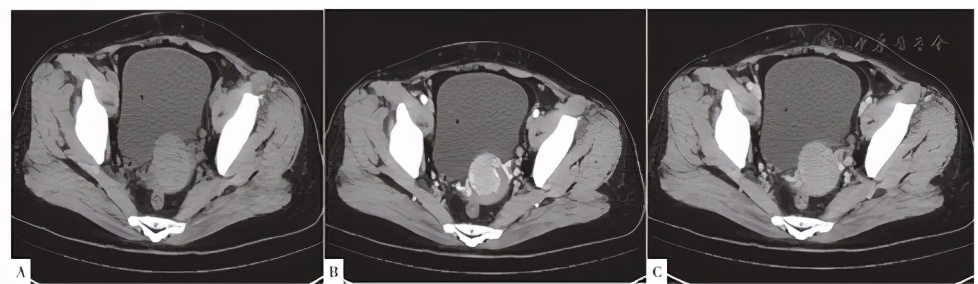

CT检查示:宫颈增粗,见一类圆形等密度占位,增强后动脉期明显均匀强化,静脉期呈等密度,边界尚清,大小31 mm×35 mm,盆腔左侧见数枚肿大淋巴结,见图1。MRI检查示:宫颈见一大小40 mm×35 mm×32 mm的占位,T1WI、T2WI以高信号为主,内见点状T1WI、T2WI低信号影,弥散受限,病灶边缘见流空血管,增强后病灶较均匀、明显强化,界尚清(见图2)。盆腔左侧见数枚肿大淋巴结。

图1 患者CT检查结果

Figure 1 Result of uterus CT scan